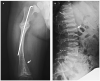

Tekrarlayan kırıklar kollarda ve bacaklarda kalıcı şekil bozukluklarına (deformite) yol açabilir ve bu şekil bozuklukları sonucu kişi ayakta duramaz, yürüyemez hale gelir. Osteogenezis imperfektalı bebeklerin oturmaları, yürümeleri gecikir. Ayrıca bu bebeklerin bıngıldakları (bebeklerin başının ortasındaki yumuşak açıklık) normalden daha geniş olur. Normalde 18 aya kadar kapanması gereken bıngıldak bu bebeklerde kapanmayabilir.

Osteogenezis imperfektanın teşhisi ve tipi bu konuda deneyimli çocuk endokrinoloji uzmanınca muayene, kan ve idrar tetkikleri, kemik grafileri ve kemik yoğunluk ölçümleri ile konulabilir. Genetik analizler ile hastalığın tipi ve kalıtım özelliği konusunda daha ayrıntılı bilgi edinilebilir.